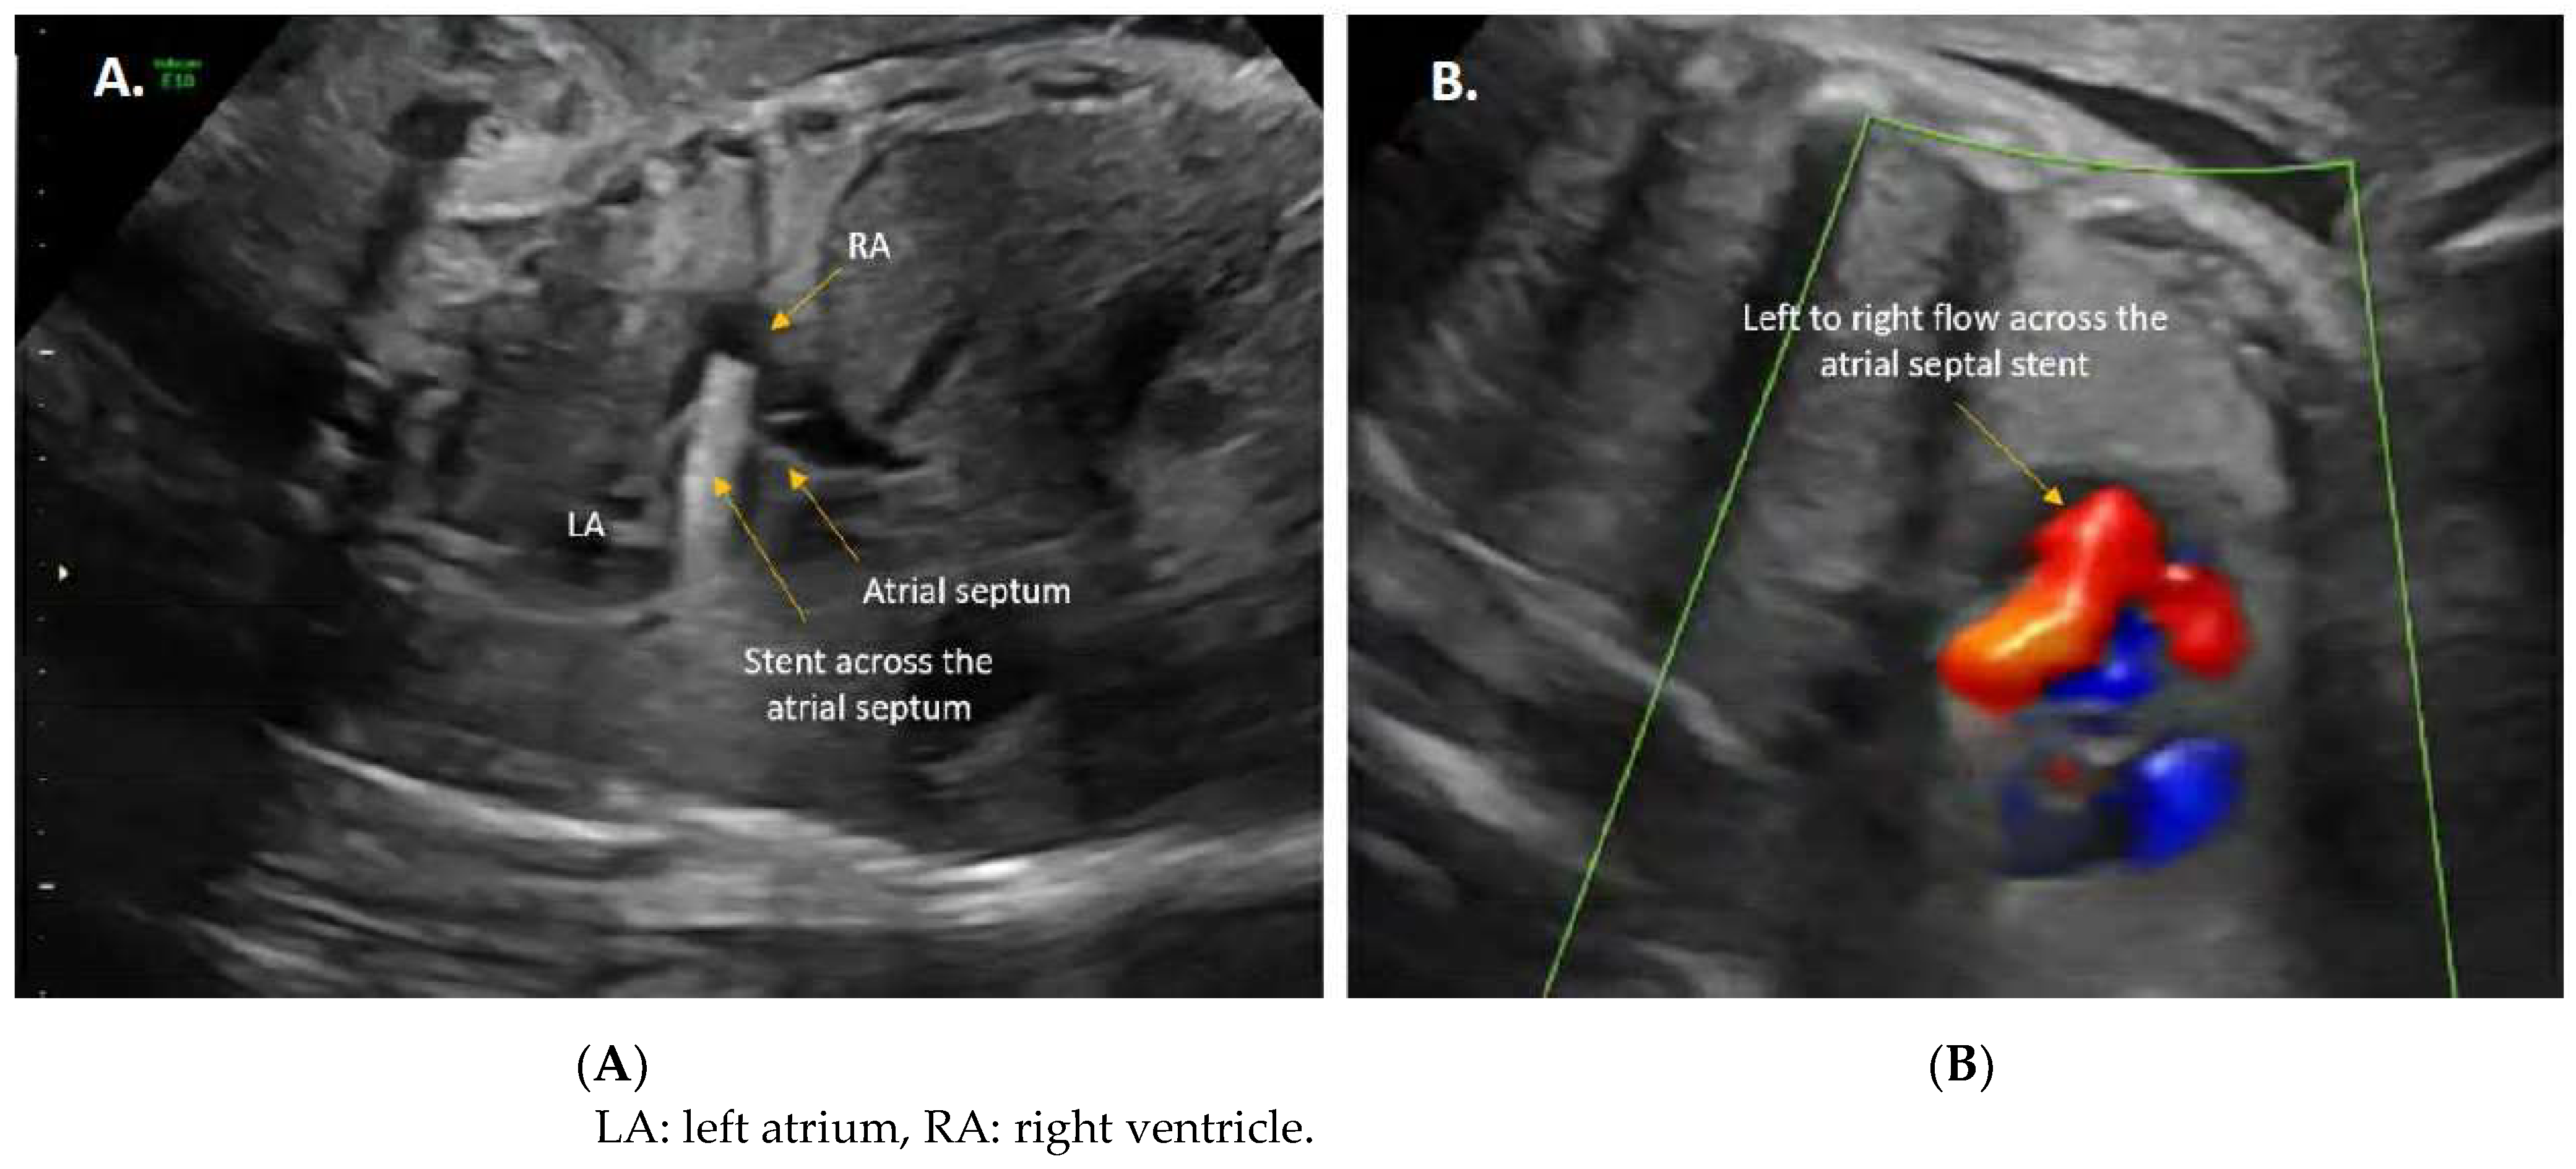

3.2. Procedural Technique

- Chaturvedi, R.R.; Ryan, G.; Seed, M.; Arsdell, G.V.; Jaeggi, E.T. Fetal stenting of the atrial septum: Technique and initial results in cardiac lesions with left atrial hypertension. Int. J. Cardiol. 2013, 168, 2029–2036. [Google Scholar] [CrossRef]

- Kalish, B.T.; Tworetzky, W.; Benson, C.B.; Wilkins-Haug, L.; Mizrahi-Arnaud, A.; McElhinney, D.B.; Lock, J.E.; Marshall, A.C. Technical challenges of atrial septal stent placement in fetuses with hypoplastic left heart syndrome and intact atrial septum. Catheter. Cardiovasc. Interv. 2014, 84, 77–85. [Google Scholar] [CrossRef] [PubMed]

- Belfort, M.A.; Morris, S.A.; Espinoza, J.; Shamshirsaz, A.A.; Cortes, M.S.; Justino, H.; Ayres, N.A.; Qureshi, A.M. Thulium laser-assisted atrial septal stent placement: First use in fetal hypoplastic left heart syndrome and intact atrial septum. Ultrasound Obstet. Gynecol. 2019, 53, 417–418. [Google Scholar] [CrossRef] [PubMed]